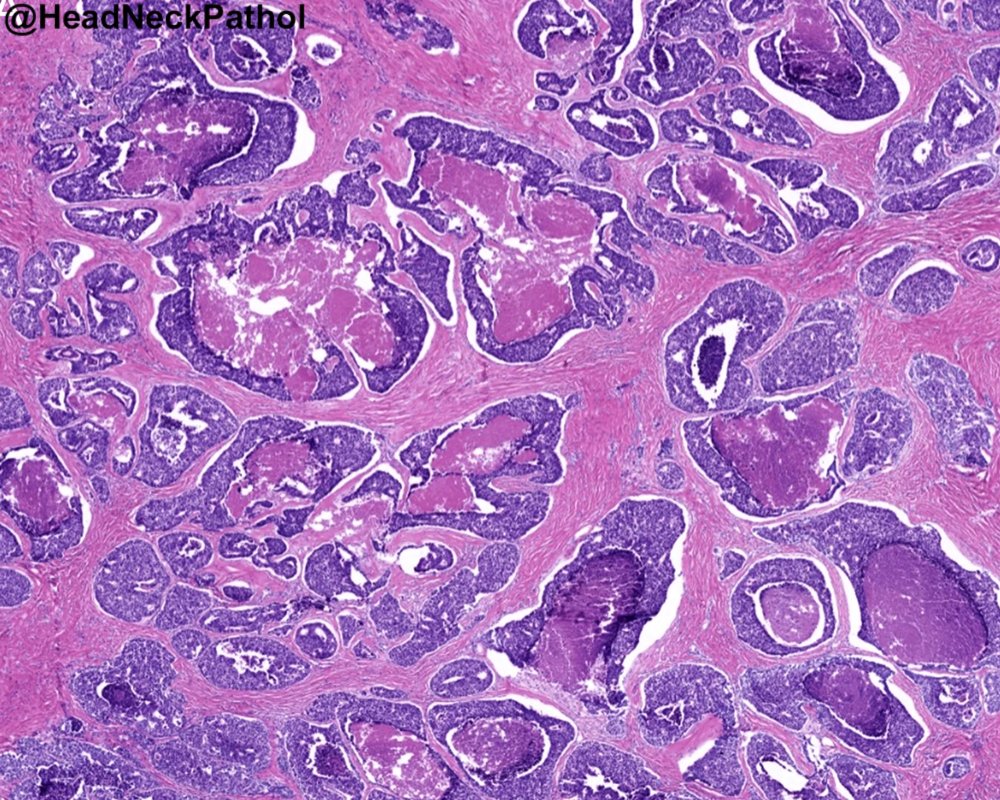

Now online: Crizotinib in Patients with Tumors with MET Amplification or Exon 14 Deletion: Results from the NCI-MATCH ECOG-ACRIN Trial (EAY131) Subprotocols C1 and C2. doi.org/10.1158/1078-0…